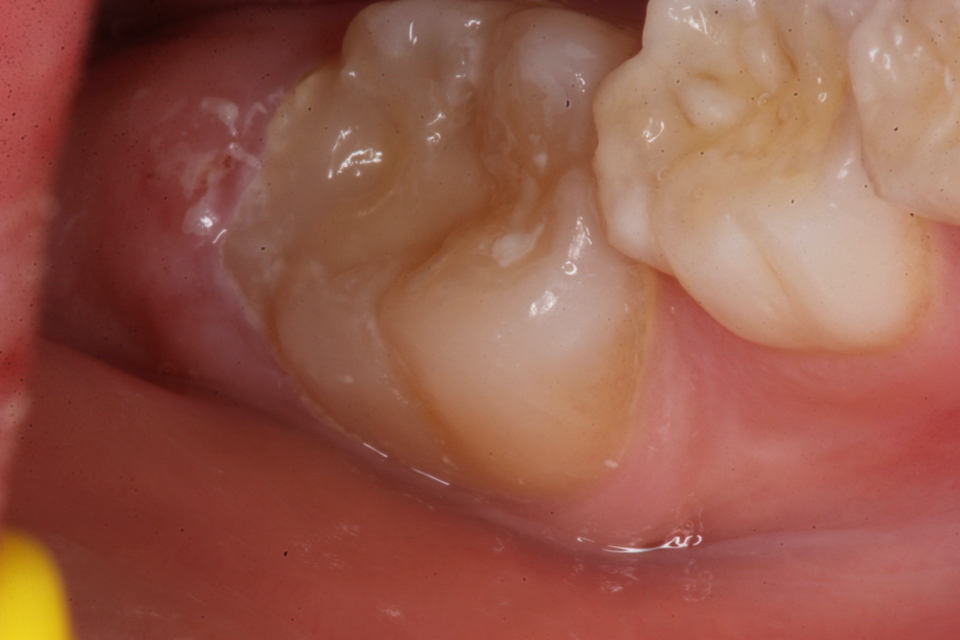

若い子の歯科治療シリーズ1.8(頬側面カリ… 2025.09.20